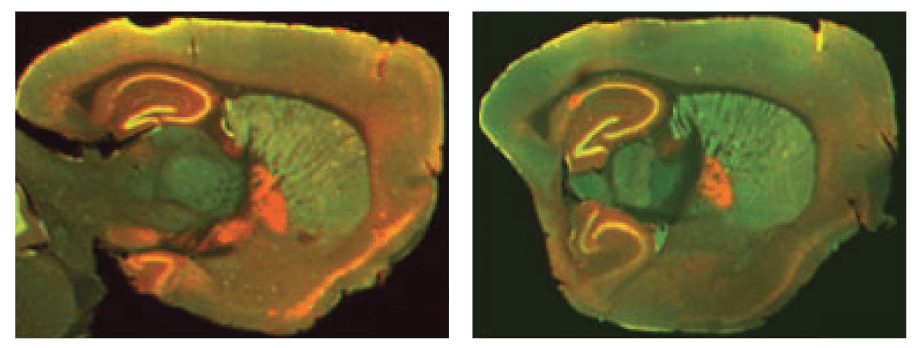

The Odyssey M, Odyssey DLx, and Odyssey CLx enable you to validate your therapeutics or probes with high-quality in vitro or ex vivo imaging. These imagers can measure uptake, localization, and biodistribution within the tissue section or organ. For example, a study by Kearn, C.S., used an Odyssey Imager to determine receptor expression and colocalization in a mouse brain to better understand Huntington’s disease markers (Figure 1).